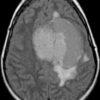

U màng não - Ảnh 2

U màng não

» Thông tin: Nam giới – 70 tuổi.

» Lâm sàng: Đau đầu.